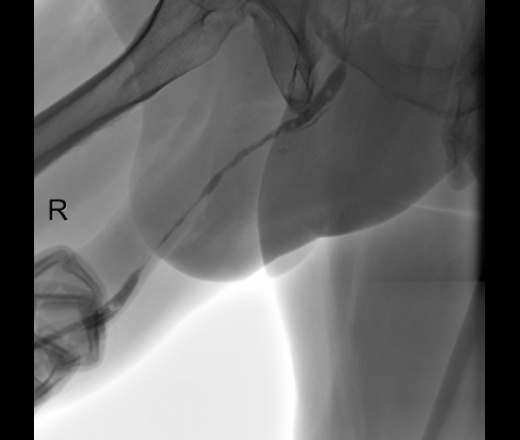

Уретероцистограмма

Мужчина  66 лет. Ищут стриктуру уретры. Уважаемые коллеги, как бы Вы расценили представленную картину?

Смотря что Ваши урологи за стриктуру принимают. По всей длине есть сужения уретры, и простатический отдел. Но, судя по контрасту в мочевом пузыре, все проходимо.

А затек контраста в мембранозной части уретры Вас не заинтересовал?

Наталия Ивановна, а чем обусловлено нарушение целостности стенки уретры?

[чем обусловлено нарушение целостности стенки уретры?

Травм не было. Расценила это так